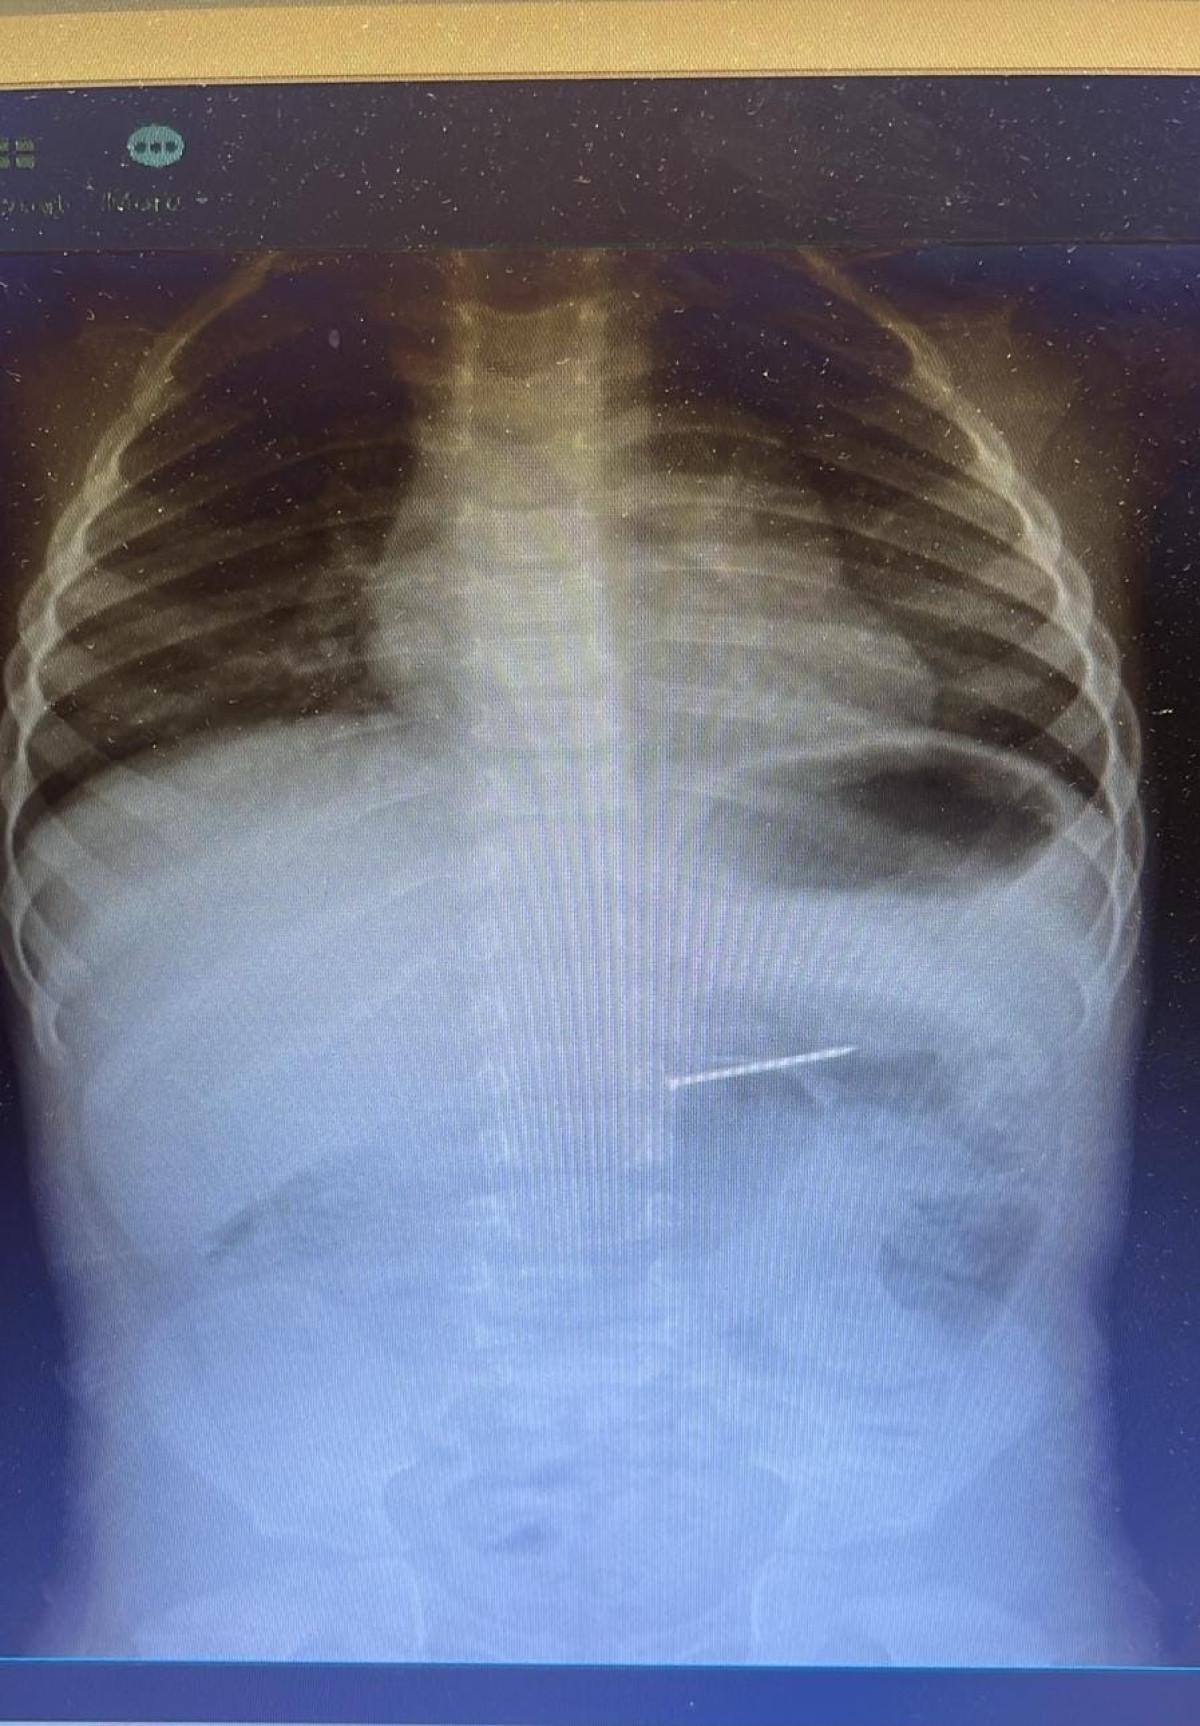

Radyolojik inceleme sonucu yaklaşık 4 santimetre uzunluğundaki çivinin midedeki konumu tespit edildi ve hemen endoskopik müdahale yapıldı.